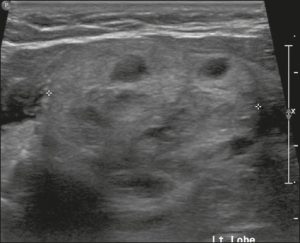

Ở đây, chúng tôi cung cấp các ví dụ minh họa việc áp dụng thực tế hệ thống ACR TI-RADS (Hình 18, 19, 20, 21). Các chú thích dưới hình mô tả chi tiết các mục đã được đánh giá và hiển thị điểm số trong ngoặc đơn.

Hình 21. Hình ảnh nhân giáp dạng đặc (2 điểm), giảm âm (2 điểm), cao hơn rộng (3 điểm), có đường bờ không xác định (0 điểm), và không có các ổ tăng âm hay bóng lưng (0 điểm). Do đó, tổng điểm là 7 điểm và mức độ nguy cơ được phân loại là TR5.